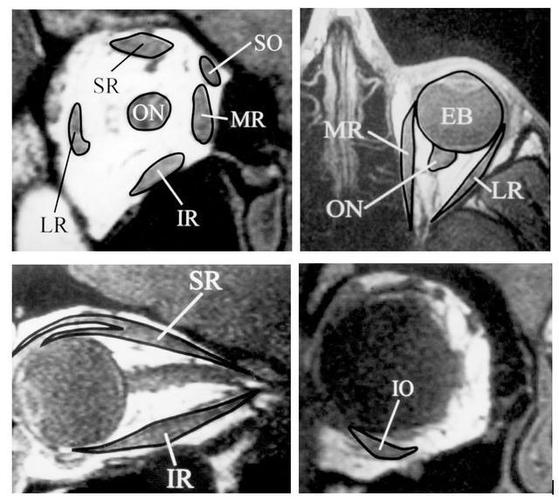

眼外肌在mri的定位 on=视神经;so=上斜肌;mr=内直肌;ir =下直肌